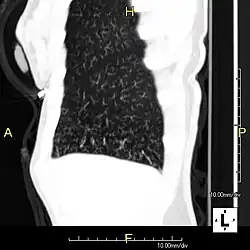

Sagittal CT image showing "tree in bud" appearance of mucous impaction in distal small airways related to primary ciliary dyskinesia